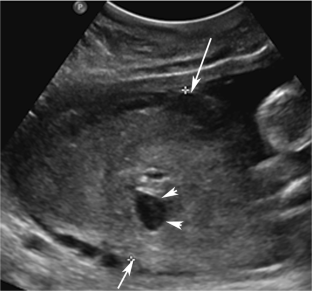

Fig. 4